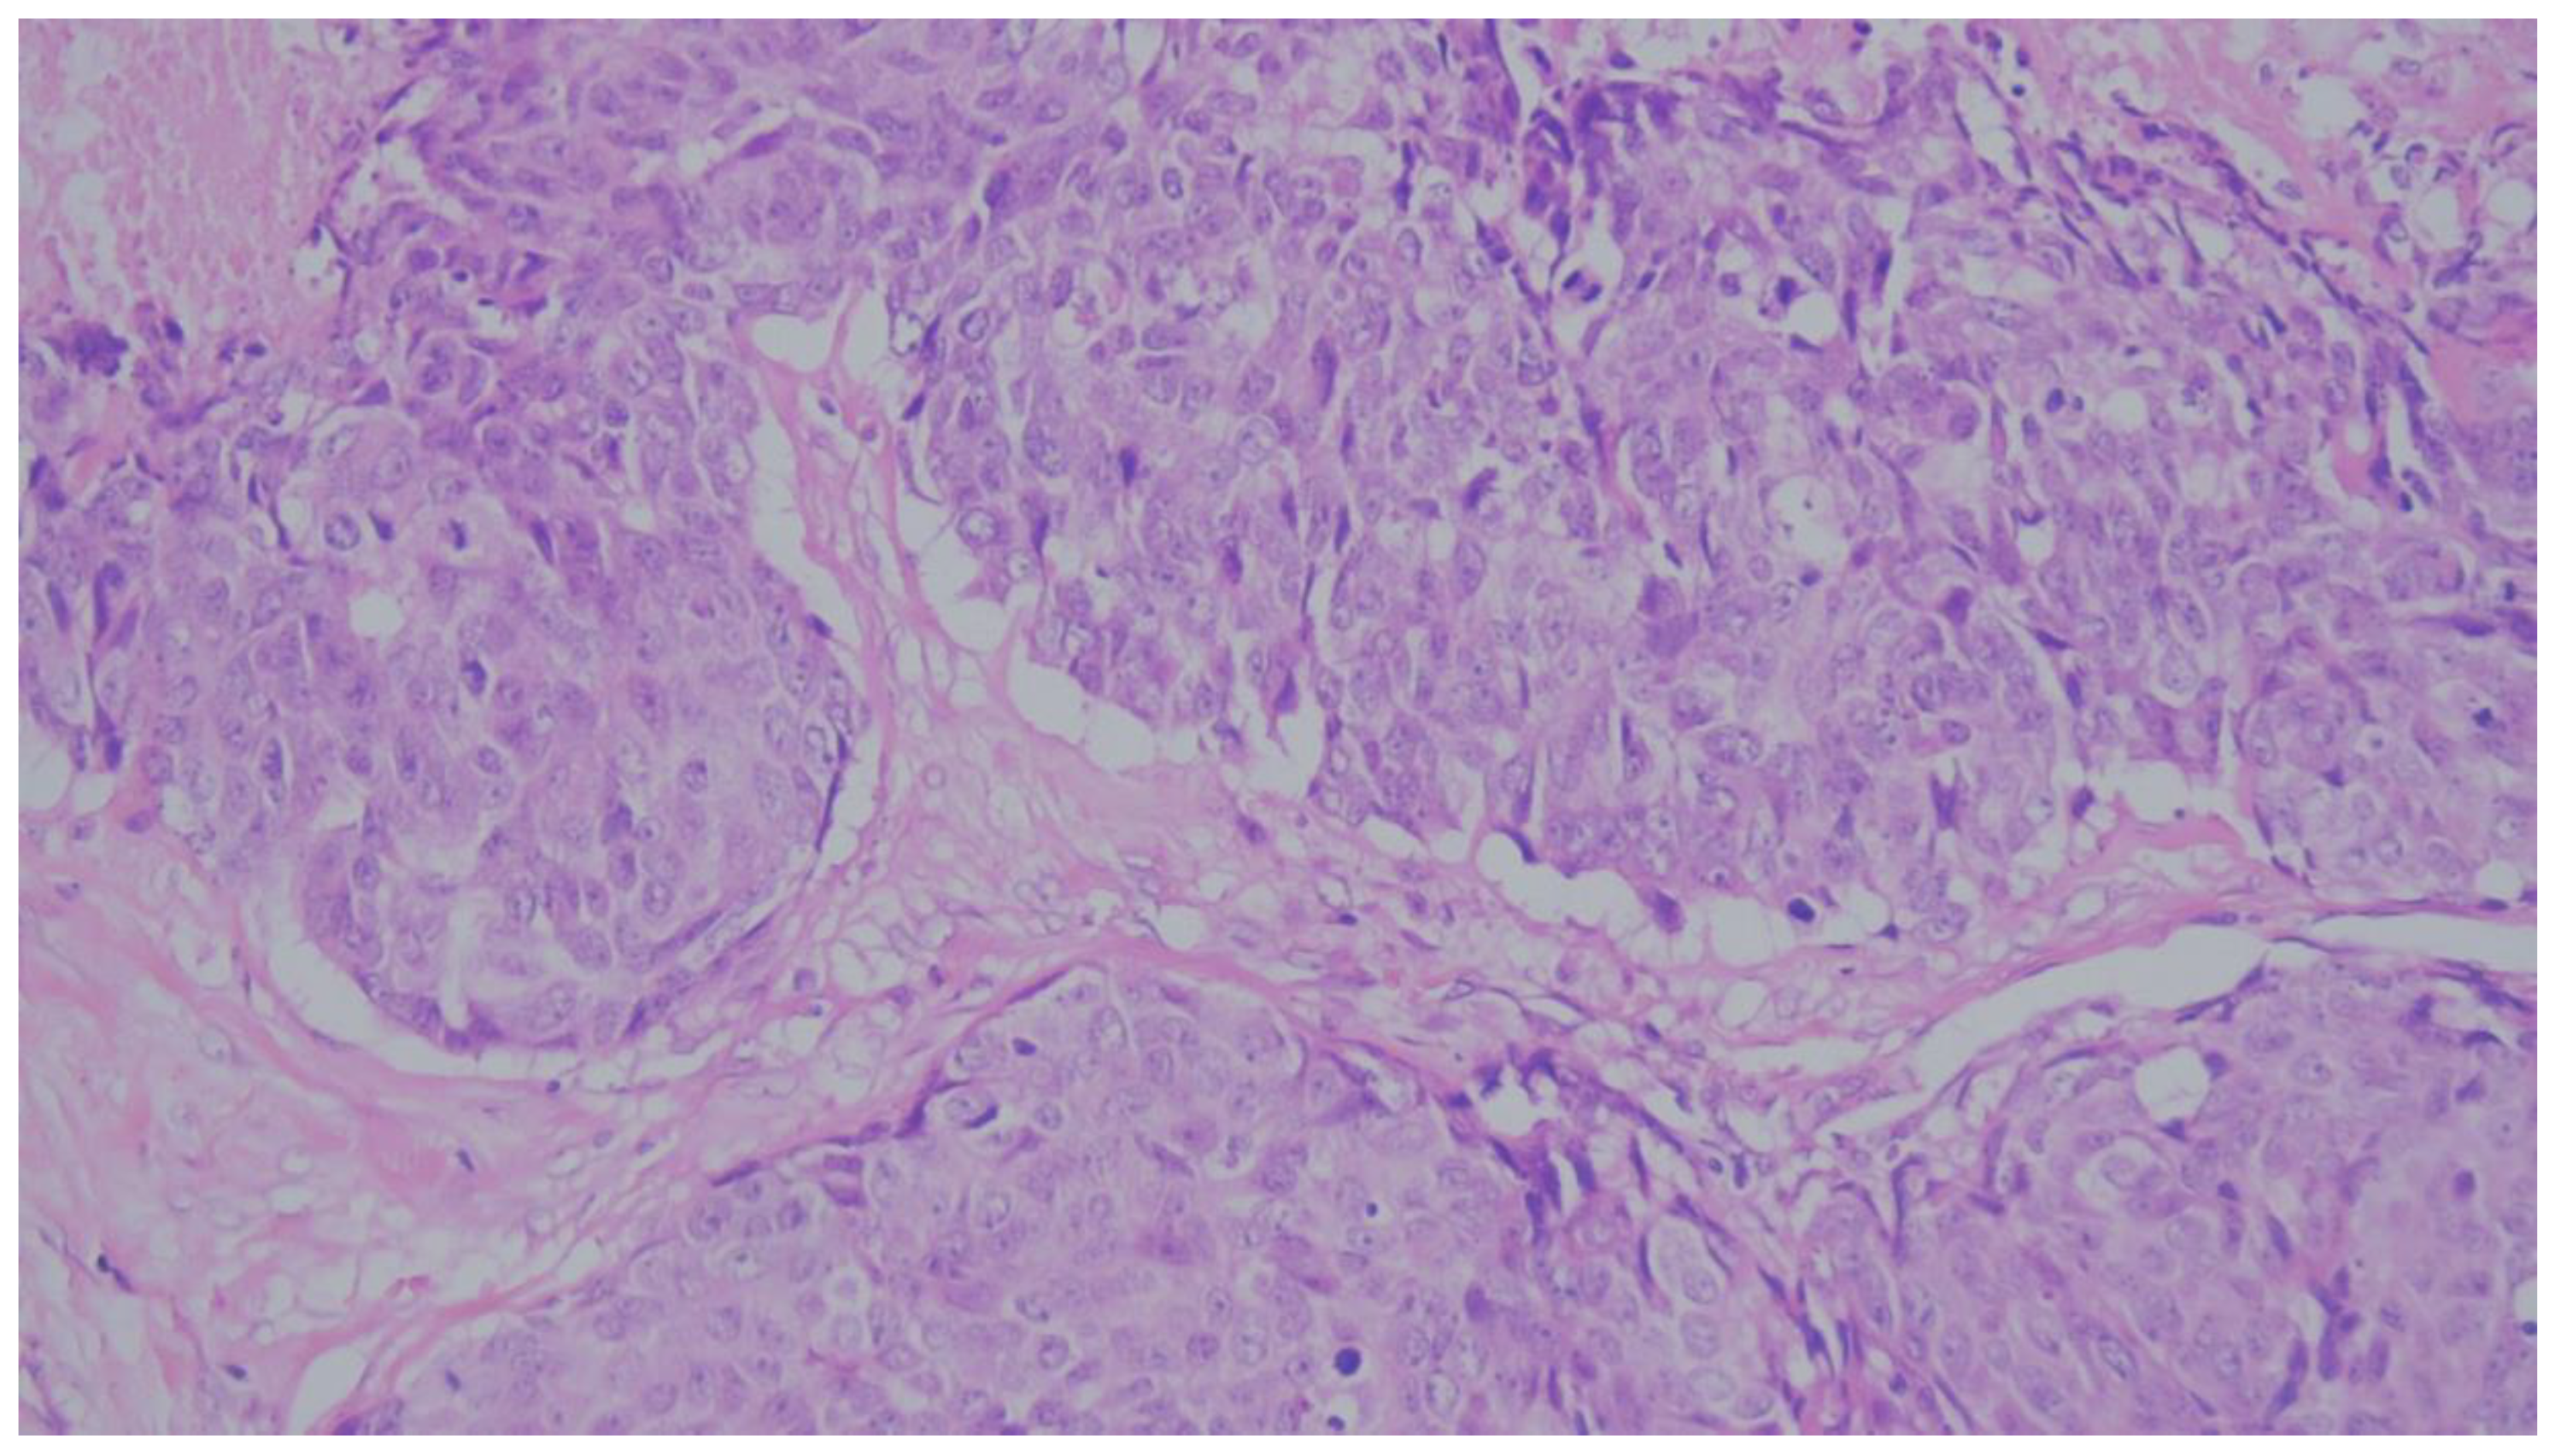

Figure 4. Representative microphotograph of a MBC displaying an “immune-cold” phenotype. There is a complete absence of significant TILs within the tumor nests and the immediate peritumoral stroma. (H&E, original magnification ×200). TILs, categorized as low (<10%).